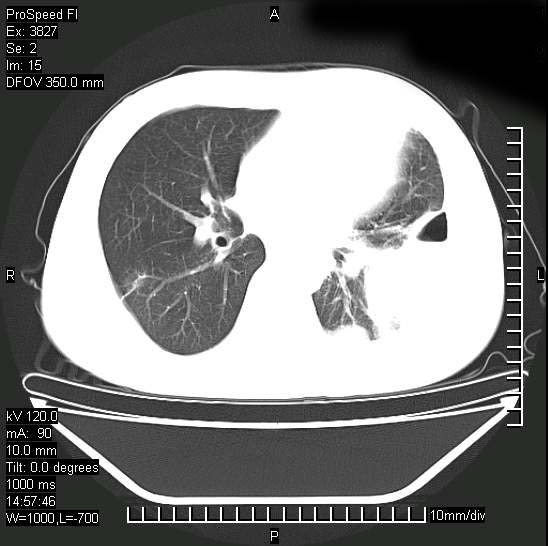

男性,一月前出现右侧肋区疼痛,较剧烈,干咳,无发热,自诉使用抗炎药后缓解,几天前又出现左侧剧烈疼痛,

发热,体温38。9,今天ct,考虑左侧包裹性脓胸,胸腔积液,右上中肺小斑片影,结核/炎症?胸水未见恶性细胞。